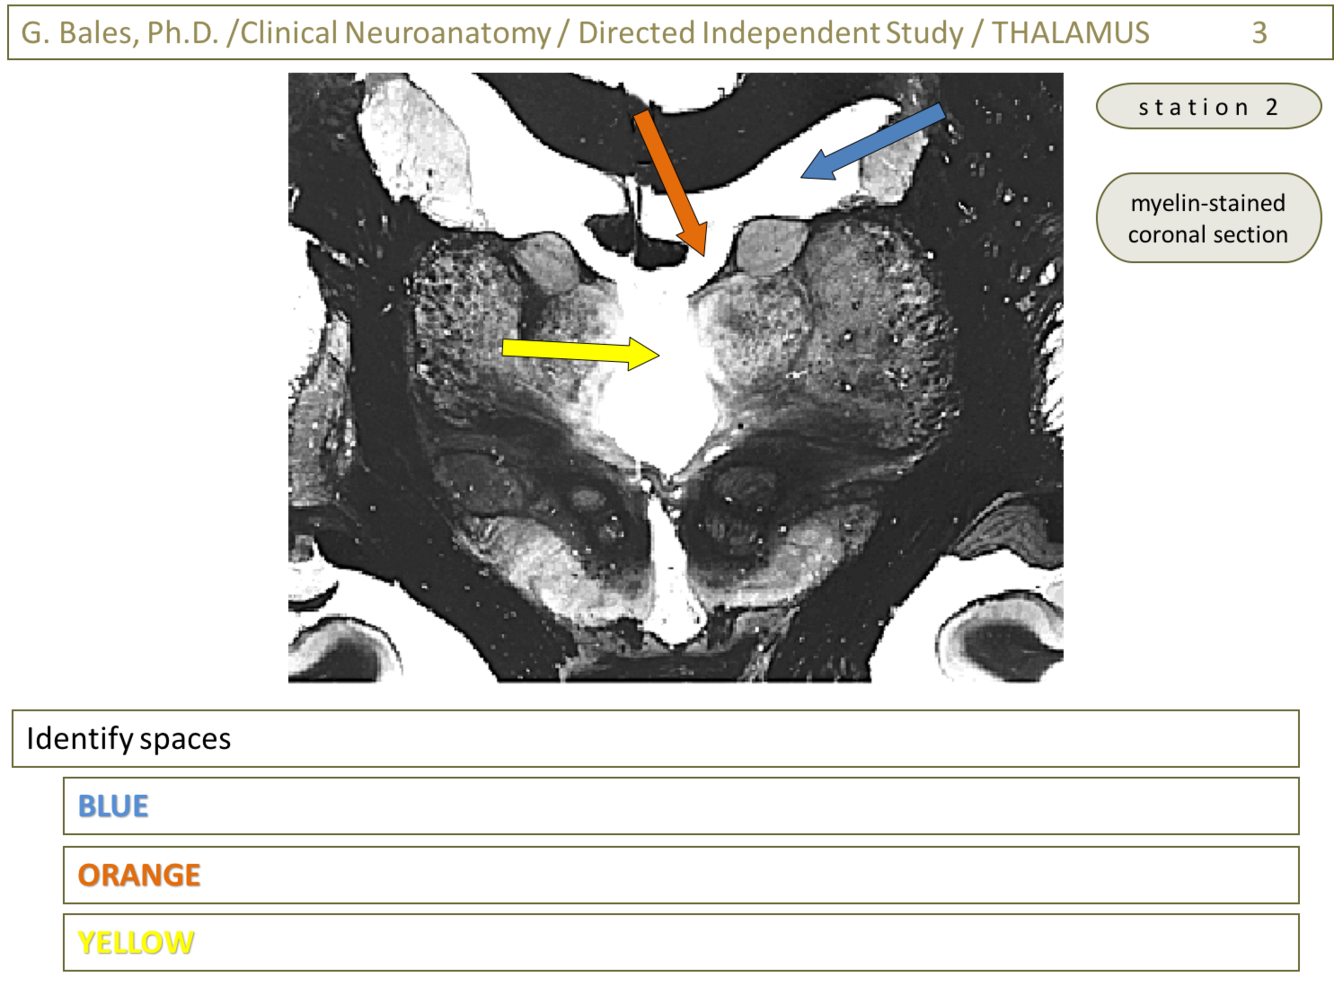

Blue – Lateral ventricle (Thalamus 2-Glass sections; slide 6)

Orange – Interventricular foramen (of Monroe) (Thalamus 2-Glass sections; slide 6)

Yellow – 3rd ventricle (Thalamus 2-Glass sections; slide 6)